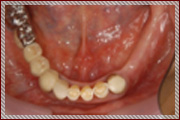

症例1

右下の奥歯の失った部位に対して、痩せた歯茎の再生治療とインプラント治療を行いました。

症例2

痩せてしまった下顎の骨を再生させる手術と歯茎を再生する手術を行い、3本のインプラント治療を行いました。